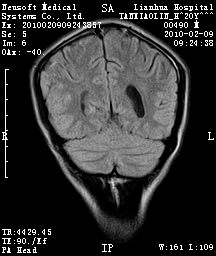

20岁男性患者,平时偶有头痛而无其他不适,现因持续头痛服药后无缓解而来院就诊。

松果体囊肿?

松果体区占位继发轻度脑积水?该患者有ct资料,我已发上。

考虑松果体囊肿。